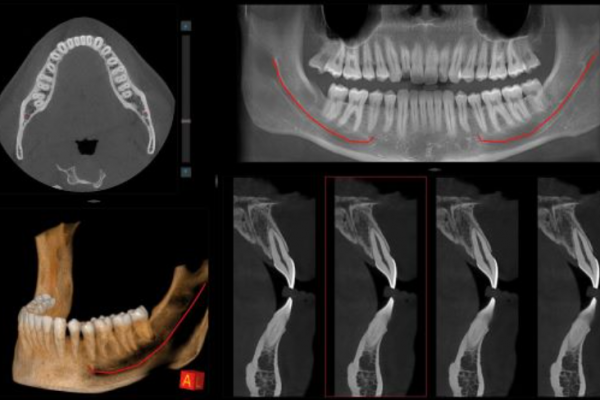

CBCT Cráneo Completo

Newton Giano

Sistema CBCT Newton Giano, líder en el sector de la radiología dental. Esta tecnología de  nos permite realizar diagnósticos detallados y precisos gracias a su capacidad para obtener imágenes tridimensionales de alta calidad del cráneo completo. Esto es fundamental no solo para la planificación y ejecución de tratamientos de implantología dental, sino también para la evaluación integral de la salud oral y general de nuestros pacientes.

Evaluación de la articulación y la mordida

Evaluar la articulación temporomandibular es esencial para garantizar la funcionalidad adecuada y evitar problemas.

Diagnóstico Vía aérea y otras patologías

El diagnóstico de la vía aérea y estructuras relacionadas es crucial para mejorar la calidad de vida.